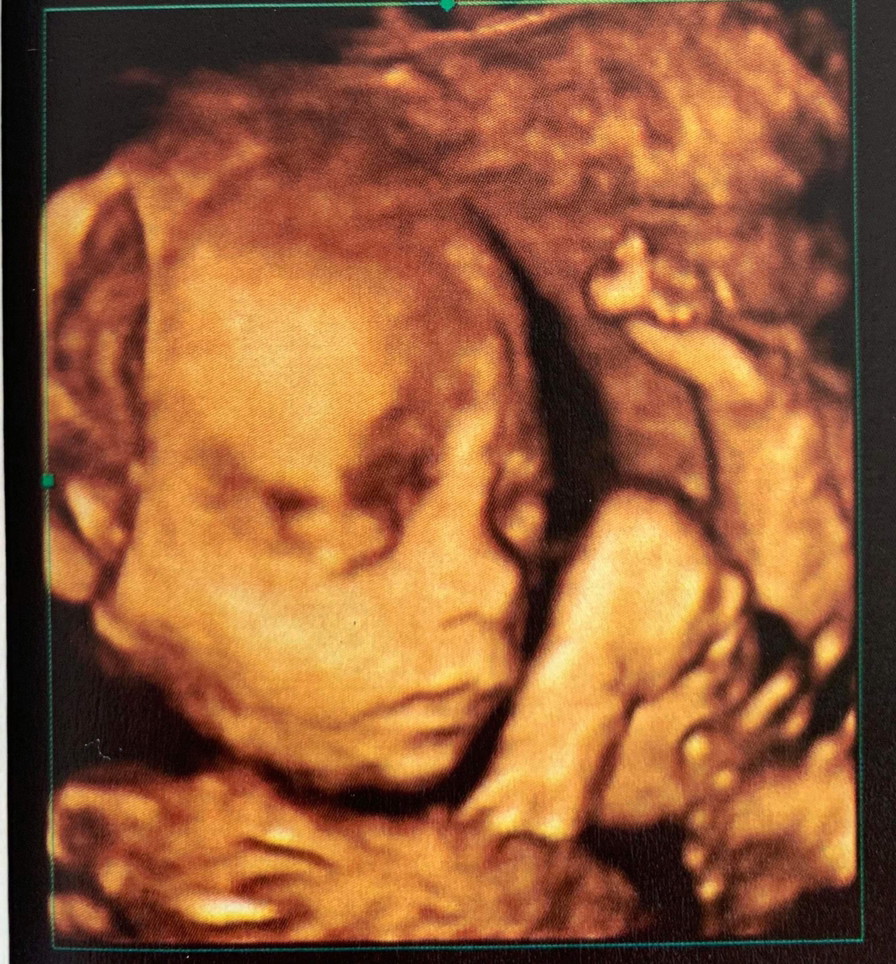

25w ผญ จ้า 3D

ใช่ค่ะชัดดี ปกติอยากซาวด์4D แต่ลอง3Dก่อน ก็ได้ภาพสวยอยู่ราคาไม่สูง ใช้ได้เลยค่ะ